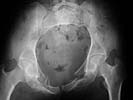

I did as suggested, I performed a 2-stage procedure (posterior sacral osteotomy and anterior take-down of left-sided rami fractures and anterior plate and percutaneous iliosacral screw fixation). It was a difficult and humbling experience. I felt as though the sacral osteotomy was complete and seemed so using intraoperative image views (inlet, outlet and true lateral of the sacrum) however after placing the distractor anteriorly I found that I could not see the sacrum well due to the bulk of the distractor itself. I then replaced it with radiolucent external fixation bars and noted widening of the left anterior SI joint.

Apparently my sacral osteotomy was not complete and the rotational correction (lateral and inferior) was occurring through the SI joint, at least anteriorly. An intraoperative x-ray showed definite improvement of the leg length discrepancy but not complete. I felt that in addition to the rotational correction the left hemipelvis also needed to move inferior as well. Due to the patient's small size, traction on her left leg simply produced pelvic obliquity and I really did not have a way of placing well leg traction which would require a post and at the same time obtain adequate intraoperative image views. Long and the short is I accepted a less than perfect reduction but with leg lengths now with less than 1 cm difference clinically and radiographically and I fused her left SI joint. No post-op nerve deficits. It was definitely a learning experience.

Any and all feed back is appreciated. Postop pics enclosed.

Probably the best treatment is avoiding this situation. Educate the individuals involved in her initial evaluation. Teach them the importance of clinical and radiographic patient evaluations. Teach them exactly how to examine an injured pelvis. If it had been examined initially, the clinical instability would have been obvious. The radiographs reveal bilateral, comminuted, displaced anterior ramus fractures along with a sacral fracture which violates the anterior, middle, and posterior portions of the sacrum (analogous to a complete sacroiliac dissociation)....a "3 column injury"(if you pretend that the sacrum is a vertebra), so to speak.

Intraoperative fluoro can be misleading regarding deformity corrections...maybe consider plain films when needed. Notice this lady's external rotation of the left hemipelvis postop and its impact on the acetabular coverage...see the inlet(caudal) view with attention to the ischial spine assymetry.